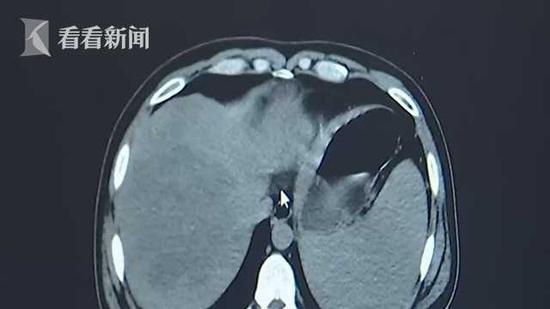

广东省第二人民医院普外二科副主任曾宪成描述道:他来的时候血脂是正常人的18倍 , 血糖是正常人的3倍 , 胆固醇是正常人的2倍 , 甘油三酯和血糖都有明显的升高 , 有明显的代谢紊乱 , 做了CT之后看到胰腺周边有很多的积液 , 建议马上做腹穿手术 。

曾副主任介绍了手术的过程:这个病人是第三天上午 , 我们跟他家人交代后 , 就做了急诊手术 , 把胰腺周围的渗液清除掉 , 切除坏死组织 , 切除部分胰腺 , 又放了几根引流管 。 当时腹腔清洗大概有2000至3000毫升的甘油三酯 。

而那种神似“牛奶”的液体正是这甘油三酯 。